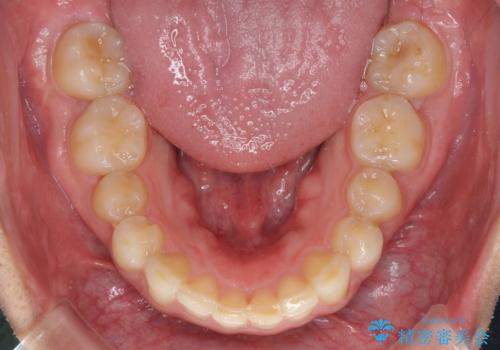

矯正治療とインプラント治療を同じ歯科医師が担当することで、通常見られるような複数医院を行き来する煩雑さや、複数担当医の見解の違いによる治療の遅滞といった煩わしさは一切なく、スムーズに治療を進めることができました。

安定して咬めるようになり、患者様には大変満足していただきました。